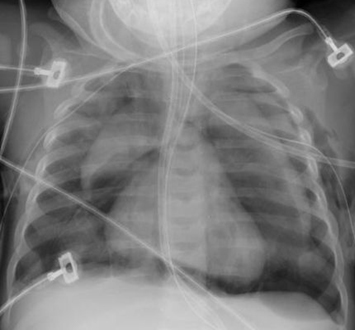

Malformação congênita da via aérea pulmonar (CPAM; antes conhecida como malformação adenomatoide cística congênita [MACC])

Do acervo de Ponthenkandath Sasidharan, MD; usado com permissão